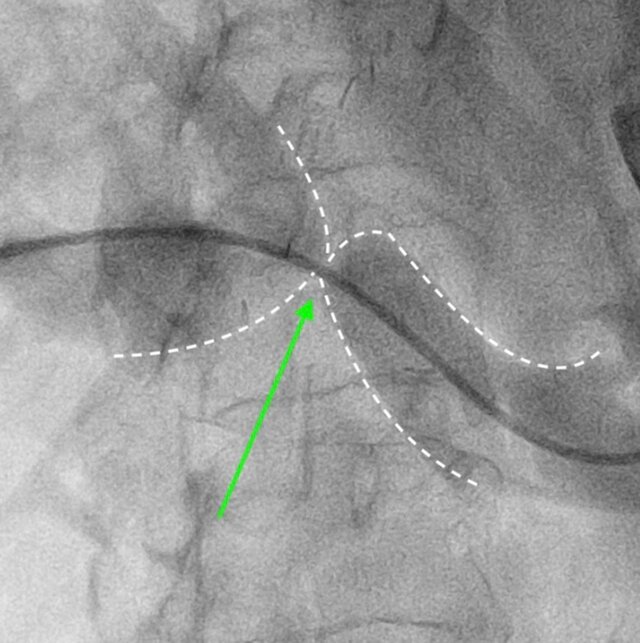

Results: All patients were treated using percutaneous transhepatic correction of portal vein stenosis with balloon plasty. In all cases ultrasound guided percutaneous approach to portal vein was performed. Balloon plasty was performed in all cases, no stents were used. No post operative complications occured. Signs of portal hypertension and graft dysfunction regressed after an average of one month of observation. There were no recurrences during 12 months of follow-up.